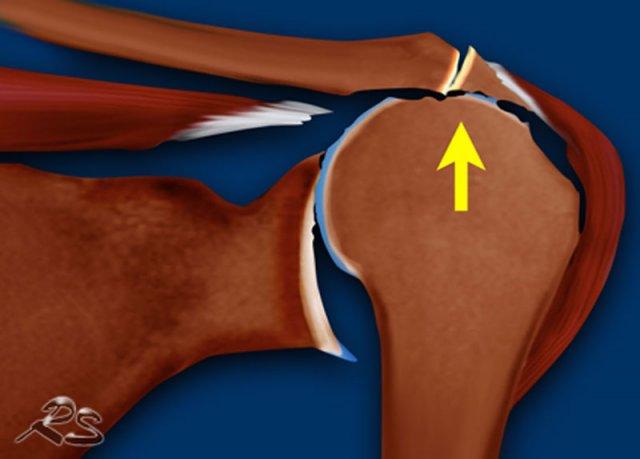

Bệnh khớp chóp xoay là một dạng thoái hóa khớp do mất chức năng ổn định của chóp xoay.

Chóp xoay tạo ra một lực hướng xuống dưới, được cân bằng bởi lực hướng lên trên của cơ delta.

Trong bệnh khớp chóp xoay, có thể gặp các dấu hiệu sau:

- Rách chóp xoay diện rộng

- Bào mòn ổ chảo, mất sụn khớp, hình thành nang và gai xương, xẹp chỏm xương cánh tay

- Di chuyển chỏm xương cánh tay lên trên với hiện tượng “đùi hóa” chỏm xương cánh tay và “ổ cối hóa” vòm cùng-quạ